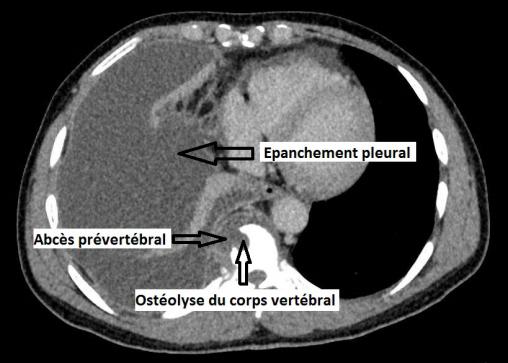

Épanchement pleural droit, ostéolyse vertébrale, abcès prévertébral

Scanner thoracique.